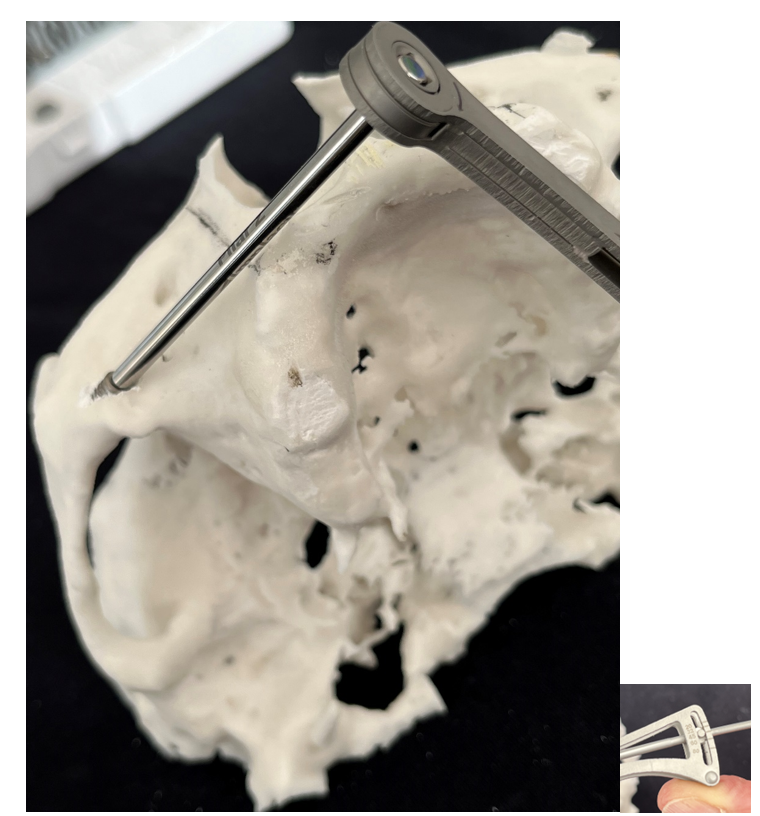

7- Simulação da instalação dos Pilares Z em biomodelo. Facilita a instalação durante o procedimento cirúrgico, altura, inclinação, local de osteotomia; quando necessário, posição da plataforma do implante, acomodação do implante no nicho da osteotomia

A montagem do Pilar Z exige do cirurgião-dentista habilidade e curva de aprendizado. Nem sempre se consegue adaptar o Pilar Z sem interferências ósseas. Por essa razão, adotamos uma rotina de instalação dos pilares na prototipagem, simulando assim, uma situação muito próxima do real no procedimento cirúrgico.

Desta forma, pode-se observar possíveis contatos ósseos no corpo da maxila ou do zigoma que não permitam o assentamento passivo do Pilar Z.

Conseguimos orientar a plataforma do Pilar Z através da chave de alinhamento, para assentamento passivo da prótese. A visualização do local de emersão do Pilar Z junto ao rebordo alveolar nos indicará onde realizar a osteotomia para confeccionar o “nicho” que abrigará a plataforma do mesmo.

Na simulação no biomodelo, os torques no parafuso do Cone Morse (15N) e na porca (20N) na junção entre o segmento B e C, deverão ser obtidos só para estabilizar o Pilar Z.

Importante que na montagem em boca, no torque da rosca que une os segmentos B e C (80 N), o parafuso fique 1/5 do seu diâmetro (aproximadamente 3 a 4 roscas), para dentro do tubo do segmento B.